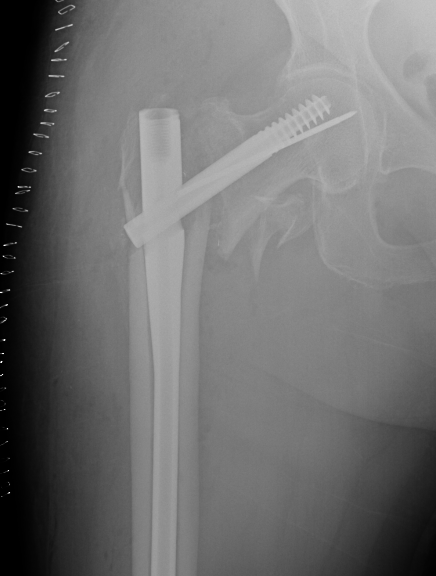

Sliding hip screw/dynamic hip screw

Cephalomdeullary nail

Cephalomedullary nail / Proximal femoral nail

Mechanical advantages

- load sharing rather than load bearing

- decreases lever arm

- supports medial cortex

Surgical advantages

- smaller incision / minimally invasive

- reduced blood loss

- shorter surgical times

Indications

- reverse oblique

- unstable fracture / loss of lateral buttress / loss posteromedial support

- subtrochanteric extension